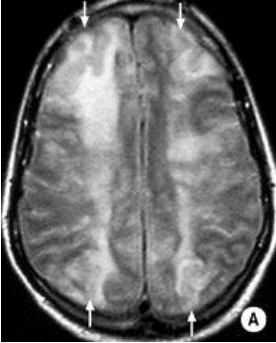

A 45 y/o woman with hypertension is resuscitated after a cardiac arrest. On day three she is able to move her face, hands, and feet, but is unable to move her limbs. A T2W1 MRI is taken at this time and is attached.

What cellular change is causing the bright vertical bands in each hemisphere?

Cytotoxic edema secondary to ischemia. The ischemia disrupts metabolism, which shuts down the Na+/K+/ATPase and causes cellular retention of Na+ and water.

Recall that on a T2W1 MRI, fluid (including water and CSF) is bright (as well as fat).

Why is the cellular change visaulized by the MRI localized to vertical bands?

This injury is a watershed infarction between the areas perfused by the ACA and MCA. The MCA area of the brain is especially susceptible to ischemia, and so its watershed area with the ACA will be the first to suffer. The bright vertical bands show cellular injury in the watershed zones across the entire cerebrum.